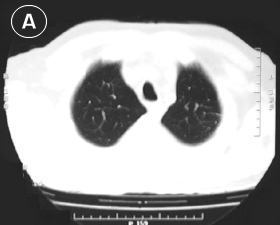

Corte Tomográfico "A"

en tercio superior del tórax:

• Corte por encima de la lesión: Parenquima pulmonar de aspecto normal traquea normal, sin evidencia de adenopatias paratraqueales.